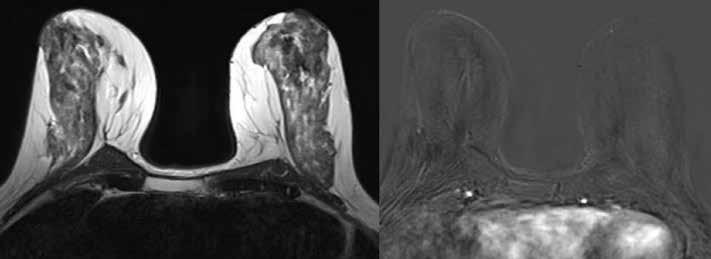

Übliche Mammographie: Patientin mit beidseitig sehr dichtem Drüsenkörper (helle Areale) und somit deutlich erschwerter Beurteilbarkeit in der normalen Mammographie.

Selbe Patientin im Mamma-MRT: Der dichte Drüsenkörper ist in der morphologischen T2-Sequenz des MRTs (links) gut zu sehen. In der für die Tumorsuche entscheidenden dynamischen MRT-Sequenz nach Kontrastmittelgabe (rechts) sieht man keinerlei Anreicherung des Drüsenkörpers, was in diesem Fall glücklicherweise einen bösartigen Tumor sicher ausschließt. Bösartige Tumore präsentieren sich im Mamma-MRT typischerweise mit einer oftmals irregulären oder ringförmigen Kontrastmittelaufnahme innerhalb des Gewebes und können dann sehr gut auch im dichten Drüsenkörper erkannt werden.